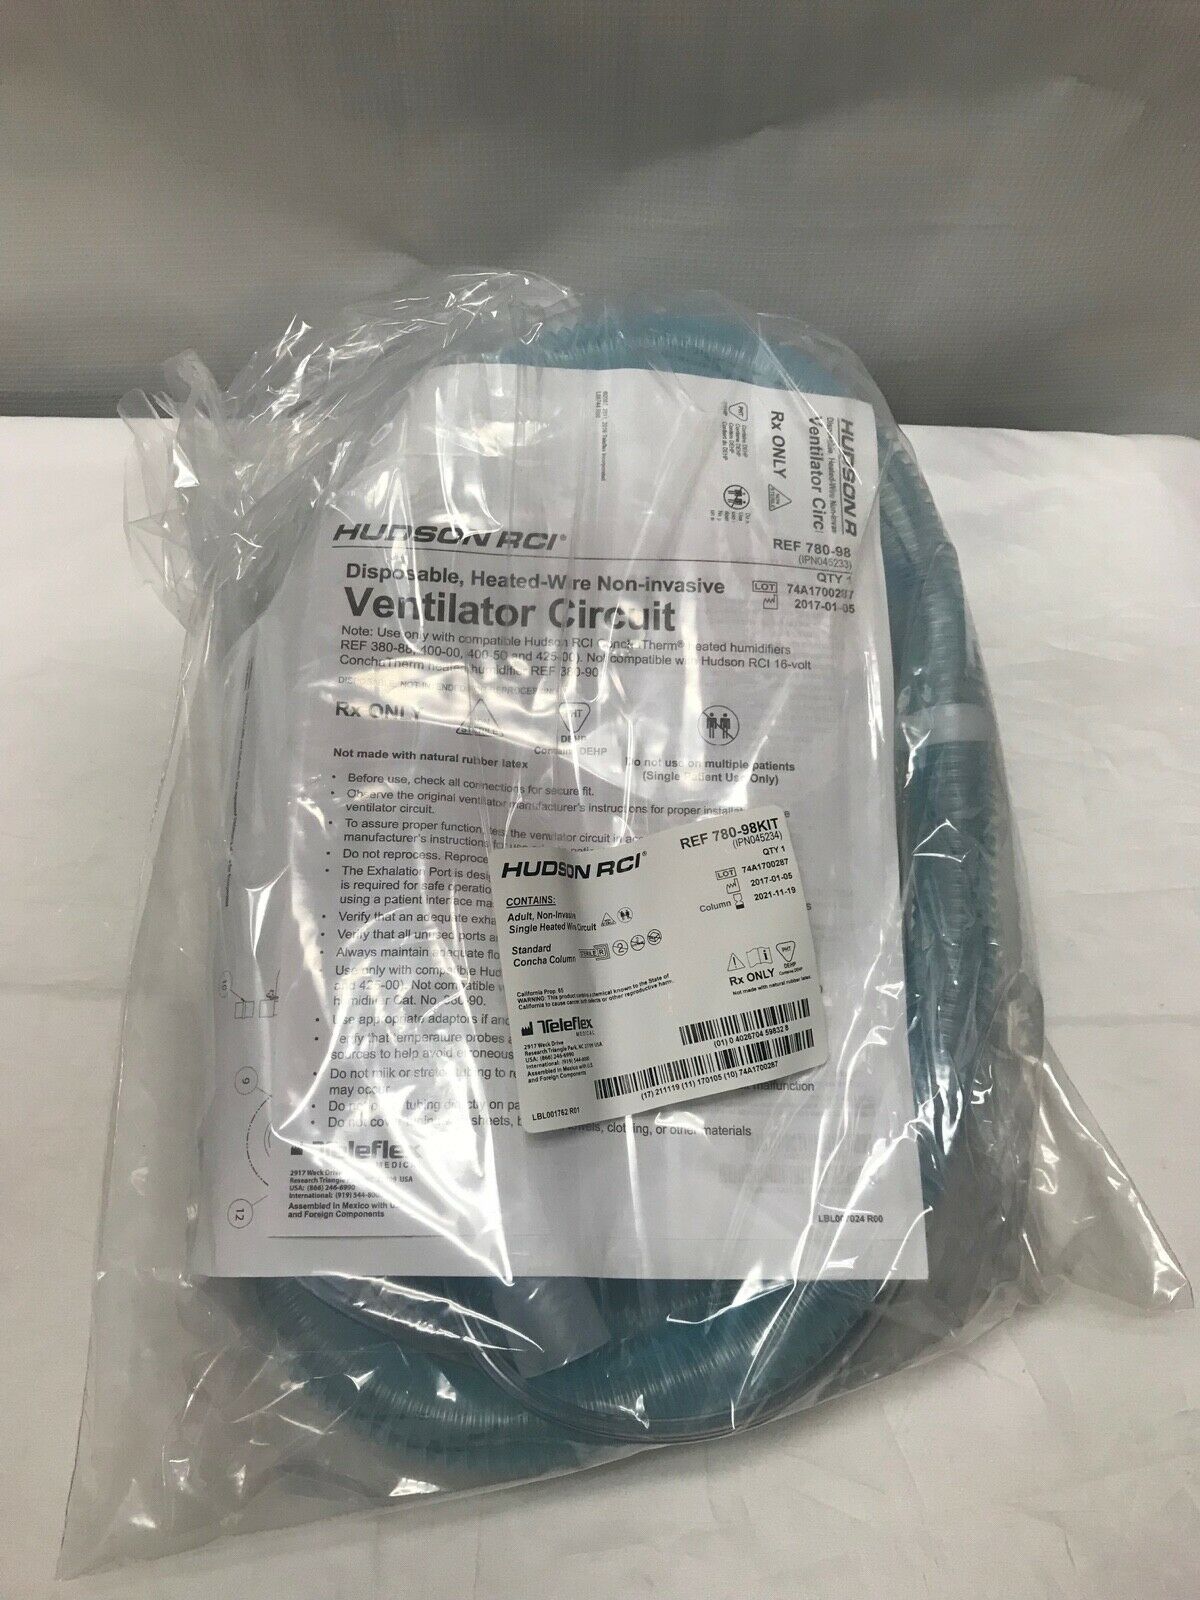

Hudson RCI Breathing Circuit with Column, Exp. 11/19/2021 (593KMD)

Sale price$ 20.50

Regular price$ 25.00